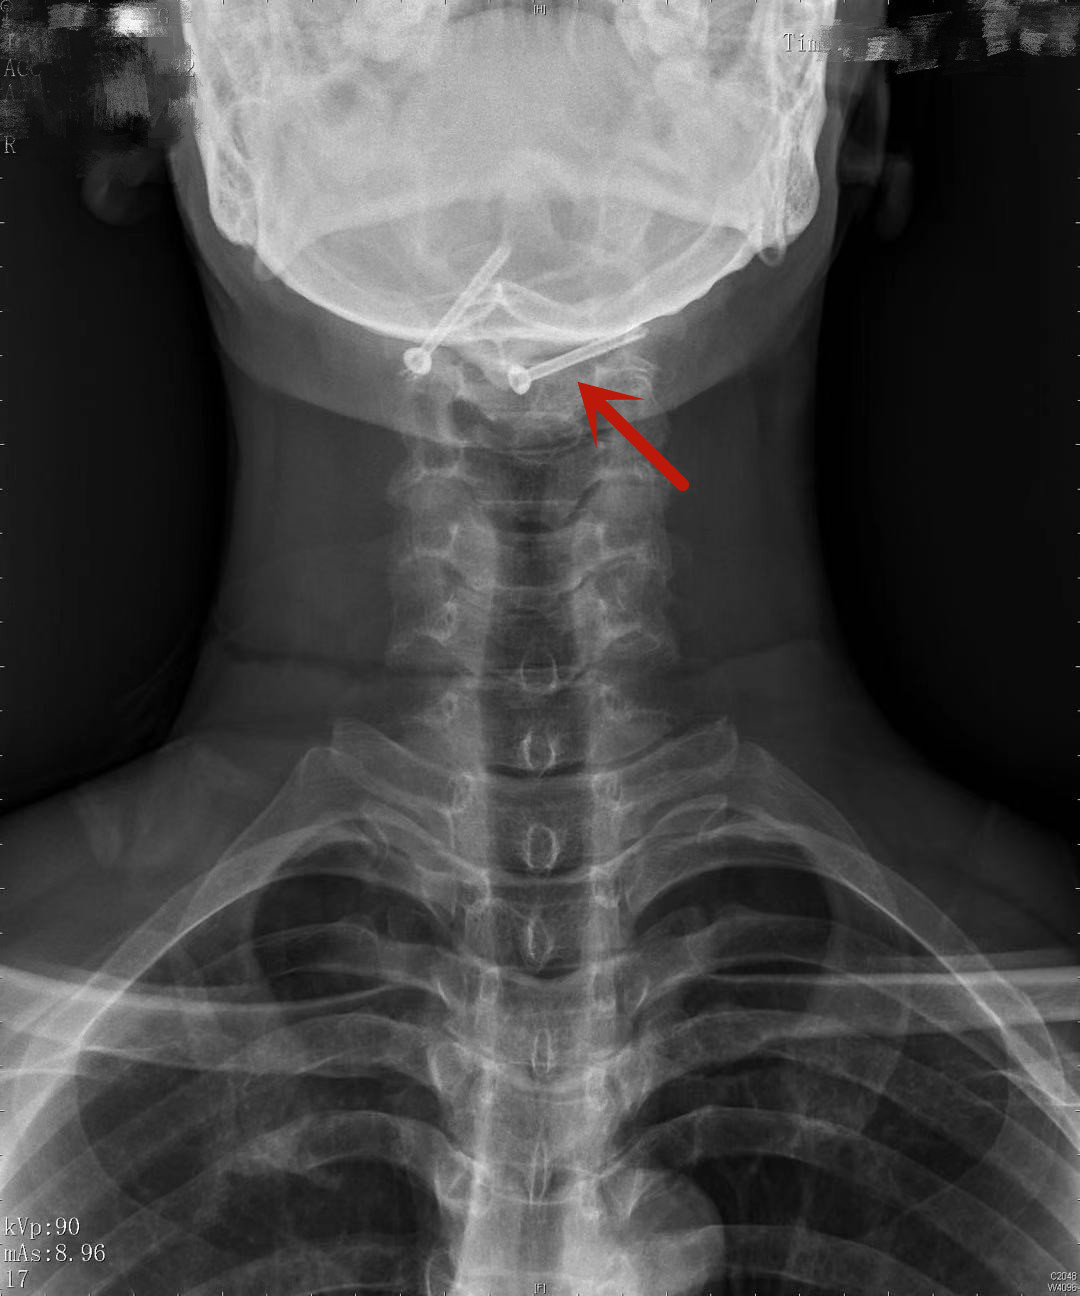

患者术后复查的影像资料显示螺钉精准地植入骨折块中

在手术台之外的控制台,是机器人的“大脑”,肖嵩华在此规划机器人手臂的置钉方案,手术过程采用“导航+机械手臂”的方式,通过术中影像资料精准定位骨折部位,规划导航路线。医师使用机械手臂按照预订路线,可直接并精准定位至骨折位置为患者进行手术,减少了不必要的开口创伤;机器人手臂同时避免了人工操作时的手部颤动,提高了手术精准度,缩短了手术与恢复时间;仅微创植入两枚空心钉就达到了固定效果,术后第二天患者即可佩戴颈托下地活动,不到一周,患者已达到出院标准。